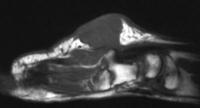

The preop MRI: